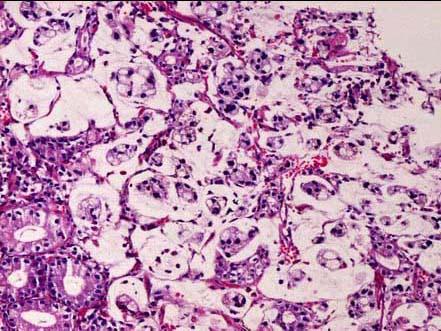

问题 患者男性,42岁,剑突下隐痛3个月。胃镜见胃窦部溃疡,直径2cm,溃疡底不平,有出血。镜检如图所示,最佳病理诊断是 ( )

选项 A.腺鳞癌 B.中分化腺癌 C.管状腺癌 D.未分化癌 E.黏液腺癌

答案 E